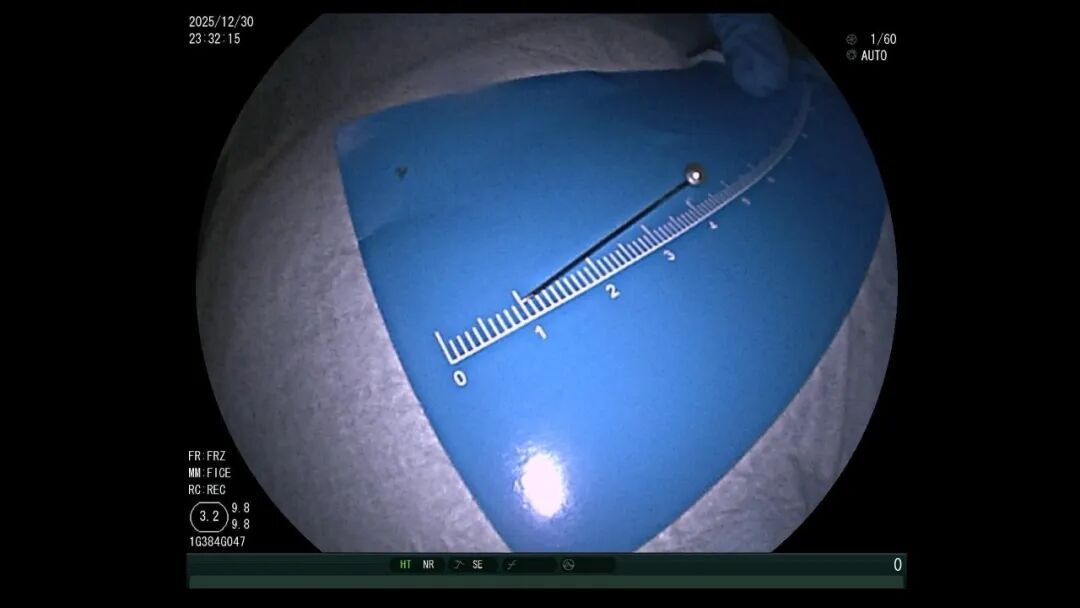

异物找不着:3.5厘米的大头针混在胃里的食物残渣中,要把它找出来,难度堪比大海捞针。

面对这些棘手情况,消化内科迅速联合儿科和普外科制定方案,经过30分钟的专注搜寻,医生终于锁定了大头针的针尖位置——它正静静“躺”在食物残渣中,银色的针尖格外显眼。

一开始,医生尝试用异物钳、网兜抓取,但大头针太滑,几次尝试都失败了。紧急调整方案后,医生改用圈套器,在透明帽的辅助下,小心翼翼地将大头针调整为竖直方,避免取出时横向划伤食管。

医生一边指导孩子配合,一边稳稳操控圈套器,将大头针牢牢固定。随着内镜缓缓退出,大头针终于被完整取出,全程未造成任何黏膜损伤。